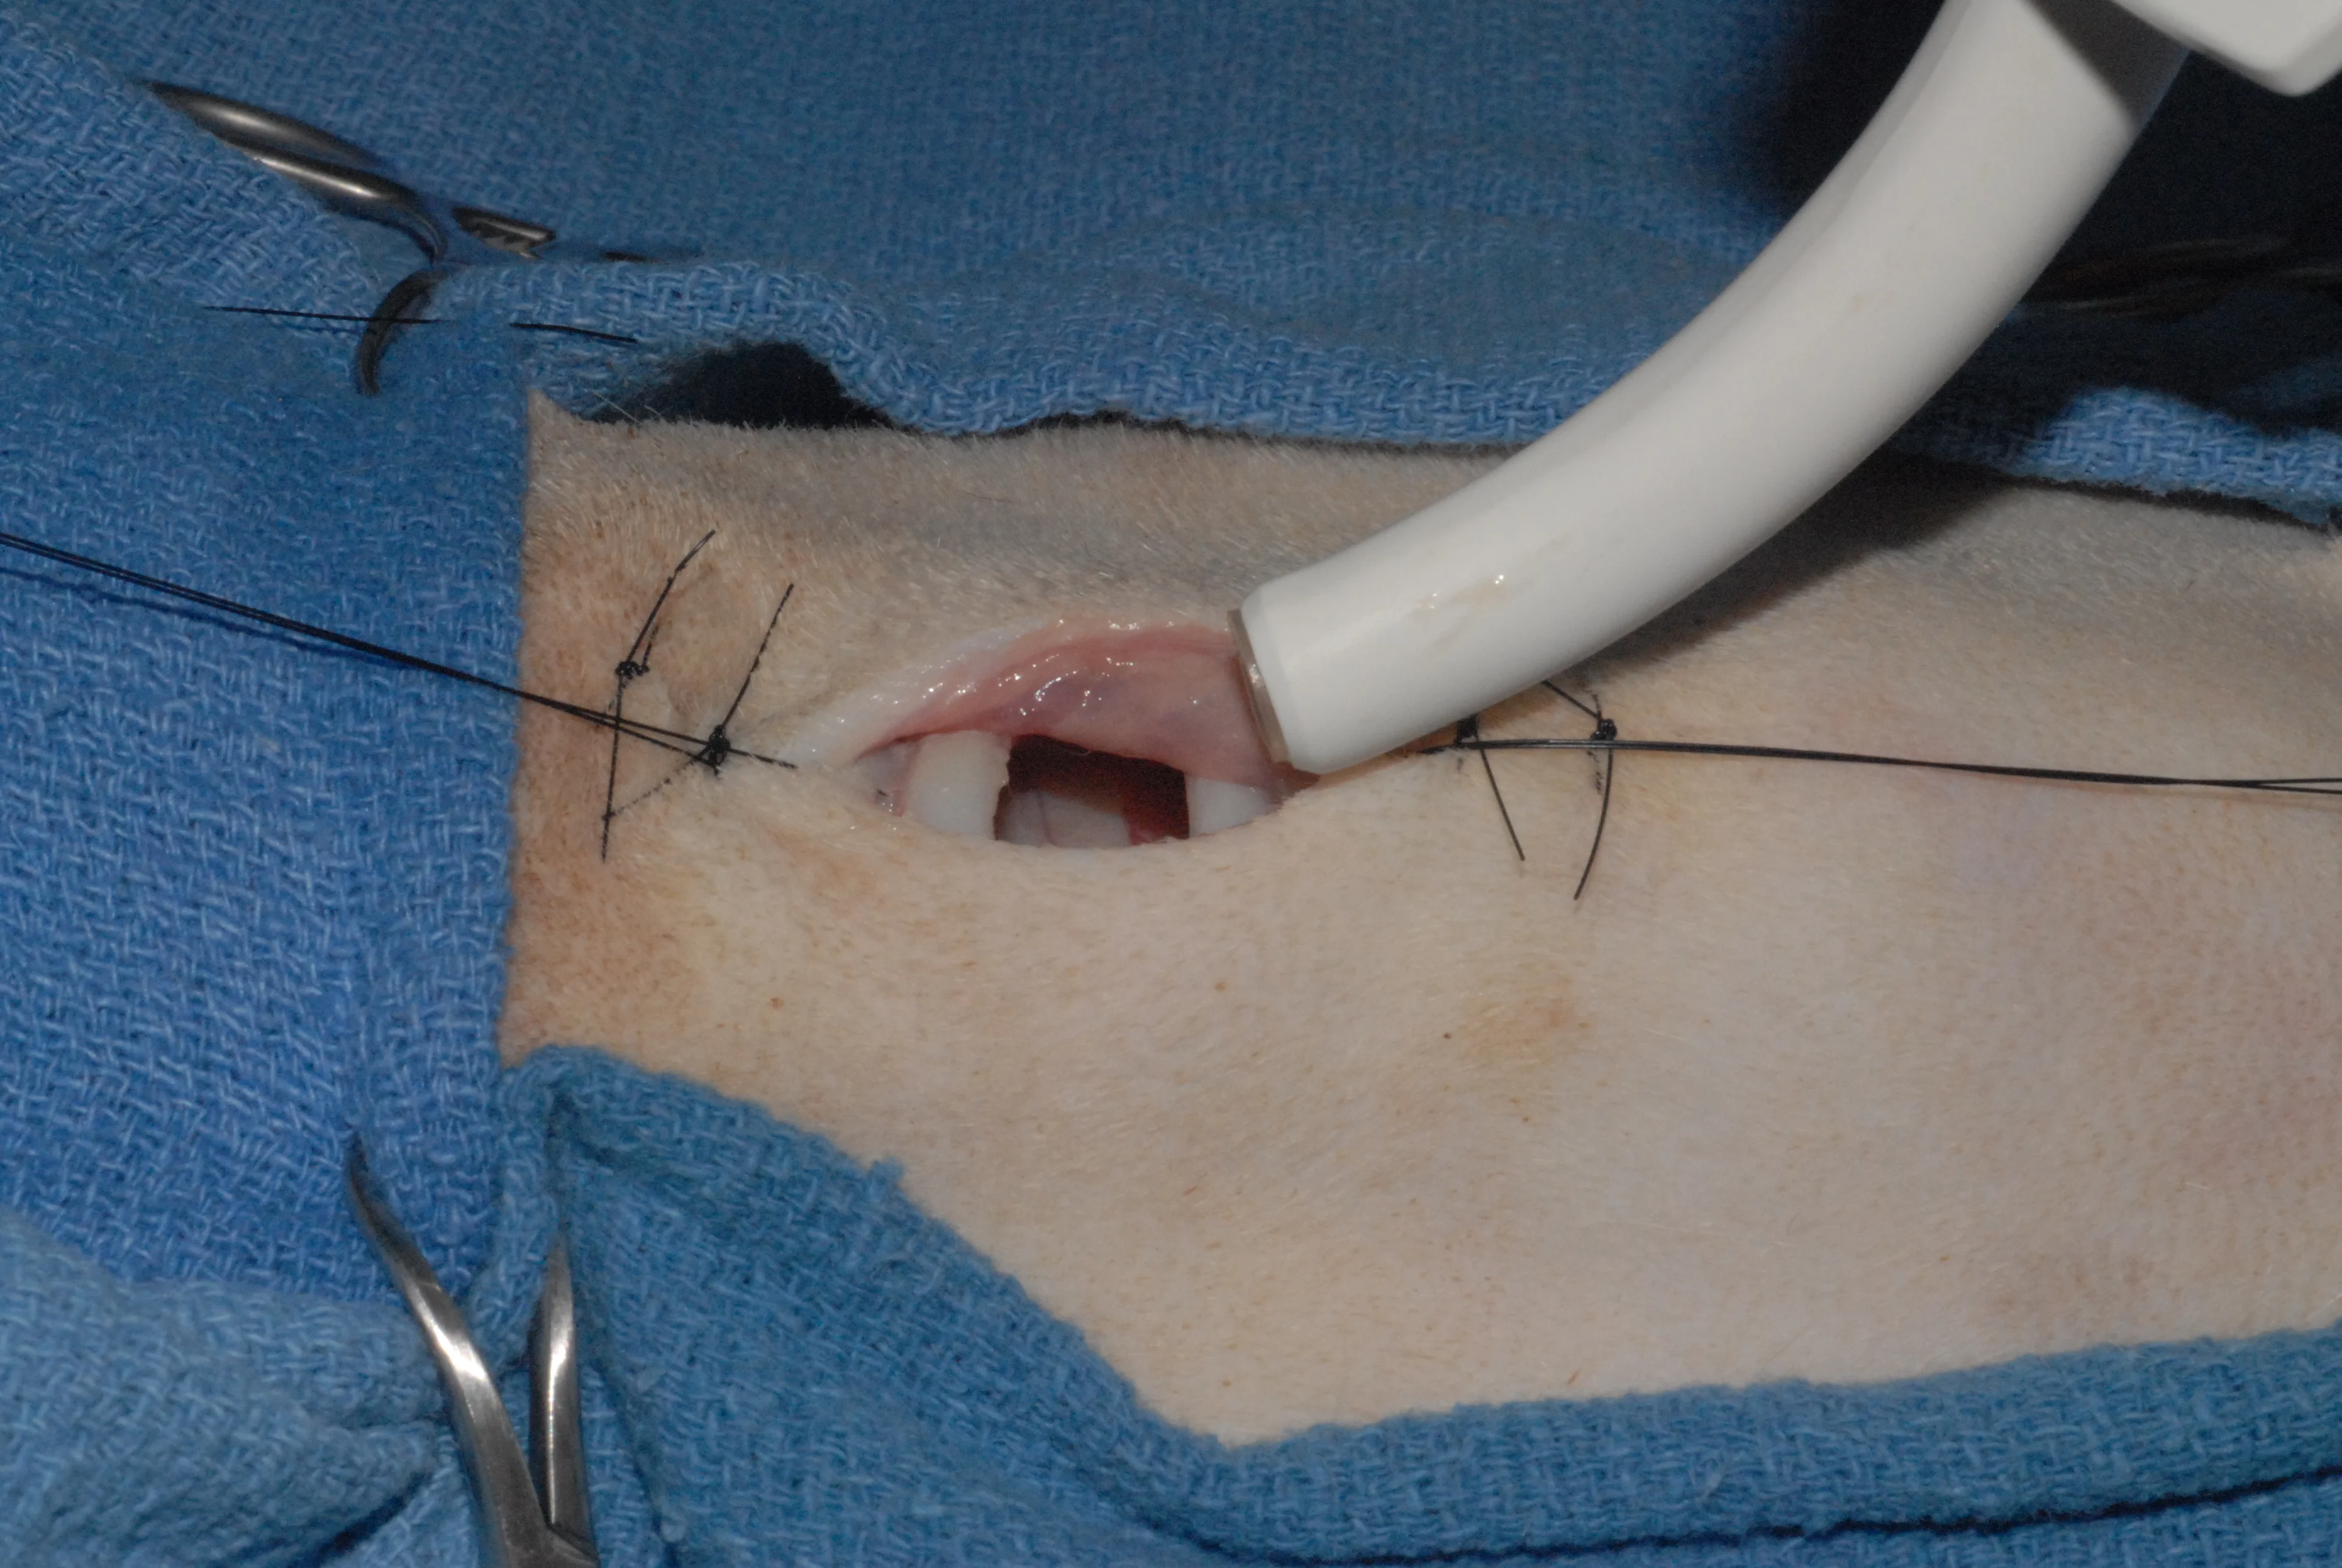

Step 9

With the tracheal incision made, the endotracheal tube is withdrawn (A) and the tracheostomy tube is inserted. Traction on the stay sutures will open the tracheal stoma for easy insertion of the tracheostomy tube (B).

A